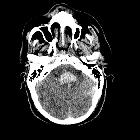

Duret hemorrhage is a small hemorrhage (or multiple hemorrhages) seen in the medulla or pons of patients who are rapidly developing brain herniation, especially central herniation.

Raised supratentorial pressure causes the brainstem and mesial temporal lobes to be forced downwards through the tentorial hiatus. As a result of this shift, it is believed that perforating branches from the basilar artery and/or draining veins are damaged with resultant parenchymal hemorrhage. Most commonly it is seen in patients with severe herniation 12 to 24 hours prior to death .

The classical appearance of a Duret hemorrhage is a single small, round hemorrhage located in the midline of the medulla or pons near the pontomesencephalic junction. Often, however, these hemorrhages can be multiple or even extend into the cerebellar peduncles.